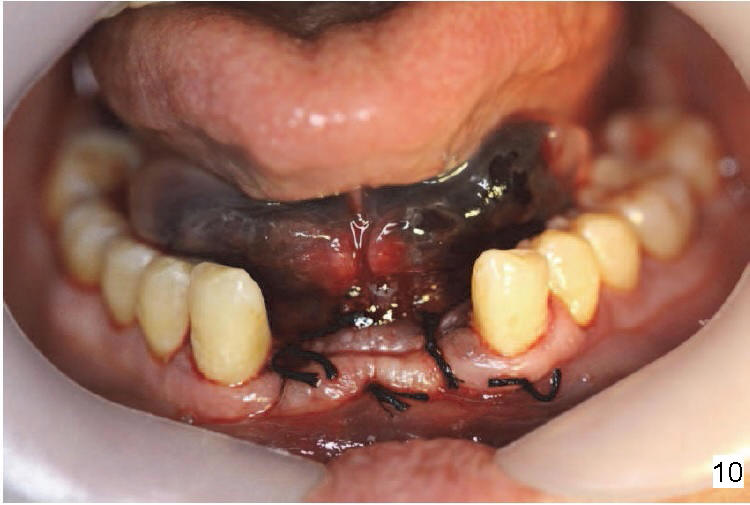

舌动脉(Lingual artery)是颈外动脉(External carotid artery)第二个前分支(图一),舌动脉末分支是舌下动脉(Sublingual artery)。舌动脉行于下颌骨舌侧(图二),它末分支舌下动脉中止于下颌骨切牙舌侧(图三),舌下动脉与颏下动脉(Submental artery,面动脉(Facial artery)分支)有吻合(箭头)。下颌骨舌侧有多个小孔(图四):正中(a, d),侧(c, e)舌孔,主要动脉穿入(1)。全景片(图五),前牙根尖片(图六)可显示舌孔(箭头, Lingual foramen)。舌孔延伸下颌骨舌侧一半(图七),下前牙植牙造成严重出血(图十,十一,2),往往是因为舌侧骨板穿孔,研究表明牙槽骨萎缩是血管意外(舌侧骨板容易破裂)主要因素(3,图八a,图九),预防方法:术前下颌骨舌侧触诊,对危险性大的病例做CT检查;术中钻洞时做下颌骨舌侧触诊,对危险性大的病例,翻瓣,暴露舌侧骨板,保护舌侧结构,使用短种植体。

口底出血好比口底感染(Lugwig's Angina),可造成窒息,双触诊临时控制出血,结扎止血最有效,及时送病人到最近医院,可能需要插管或者气管切开。